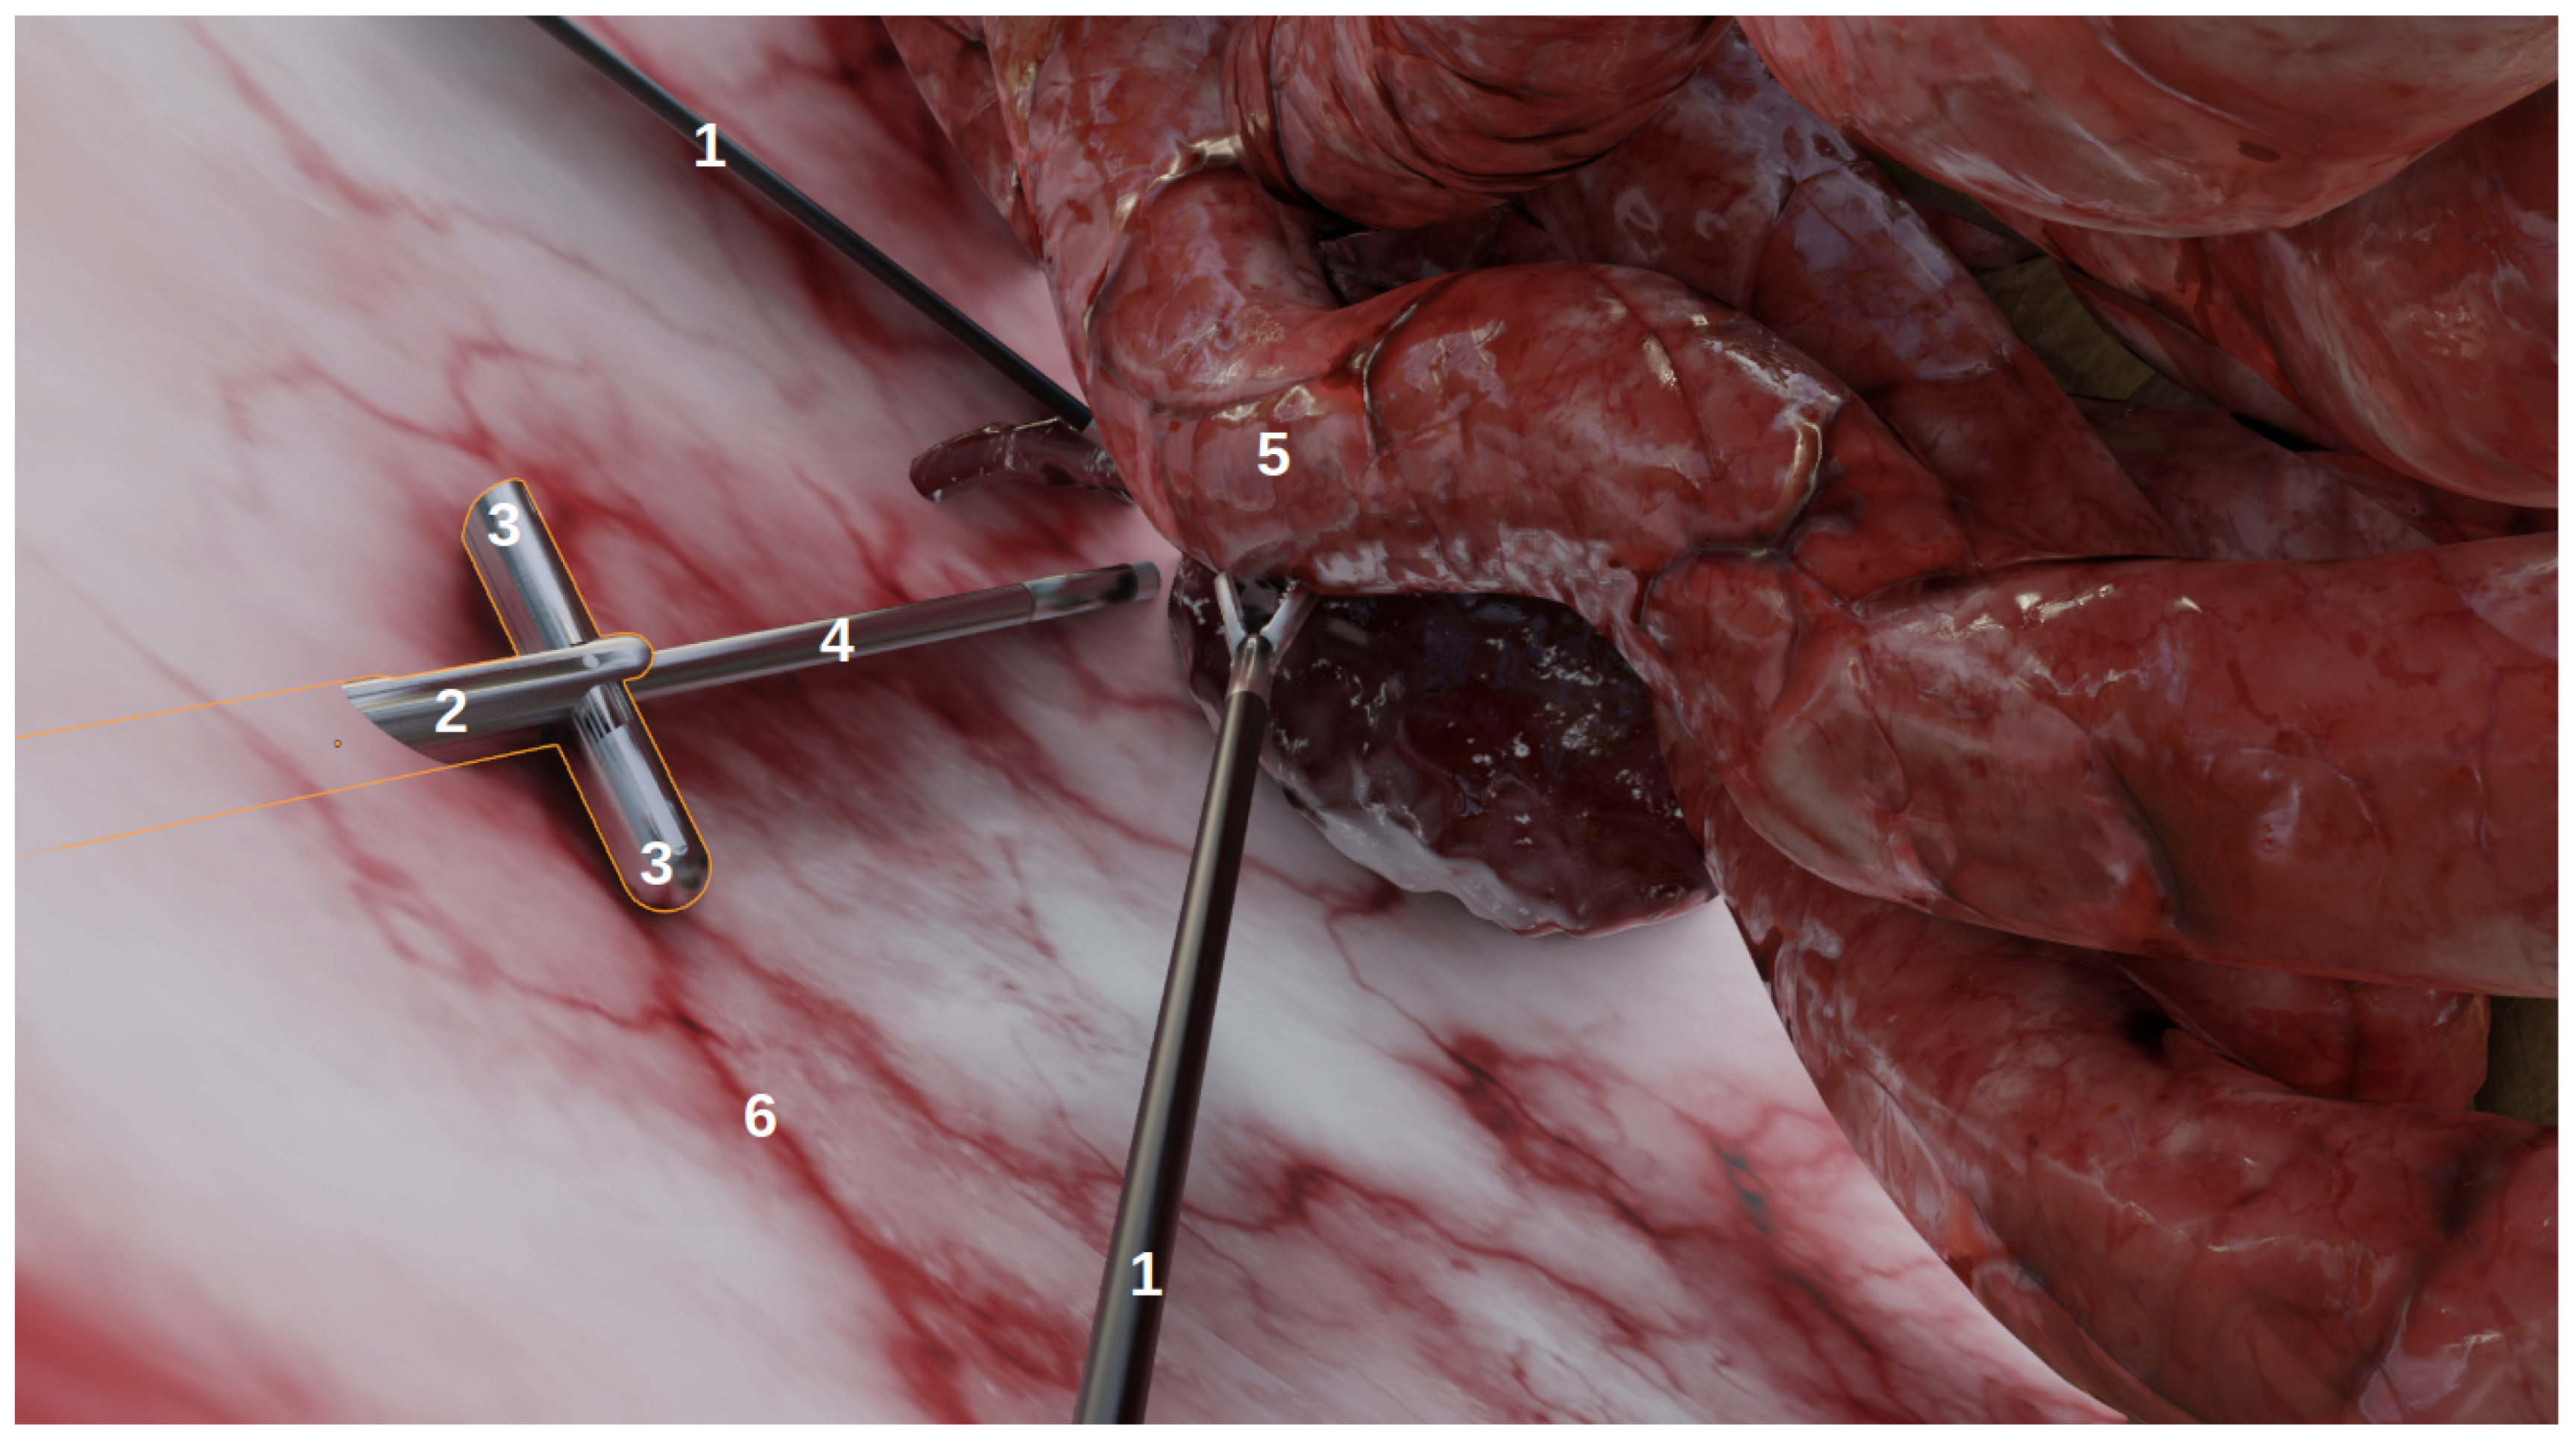

The goal of this environment, developed using Blender (http://www.blender.org (accessed on 6 January 2022)), a 3D modelling and rendering software, was not to achieve anatomical realism, but rather to produce images that could realistically represent laparoscopic conditions as viewed from laparoscopic cameras. As shown on Figure 1, it contains:

Figure 1.

The simulated environment viewed from a user perspective in Blender. This is not a camera perspective and thus, does not include the rendering (e.g., illumination, shadows). (1) The laparoscopic forceps, (2) the multi-camera prototype, (3) two deployed cameras, (4) the endoscope, (5) organs, (6) the abdomen.

- Organs, with corresponding realistic image textures, e.g., intestines, blood vessels, abdomen;

- Tools: laparoscopic forceps and a 5 mm endoscope with LEDs;

- Multi-camera prototypes, where the number of cameras and their focals, FoVs and inter-spaces can be modified. In this study, we simulated the multi-camera prototype of [6] with two deployable Misumi TD-VBL31105L-77 cameras (1.83 mm focal, 69° × 43° FoV) and an inter-space of 4.5 cm. These specifications were established according to the results of a specifically performed experiment, provided in Supplementary Material Figures S4 and S5, which showed that this was a good compromise between overlap and the enlargement of the field of view.